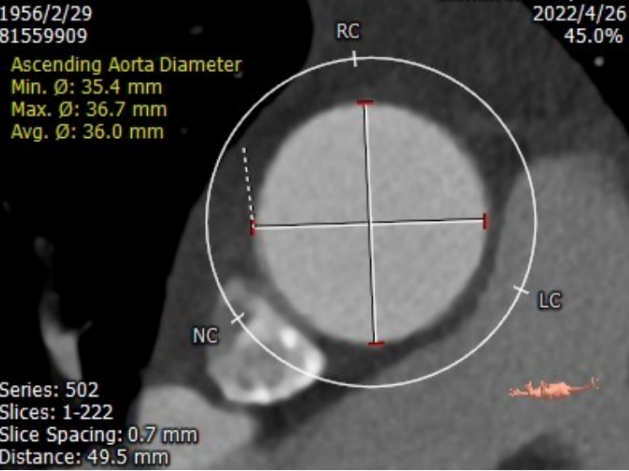

升主内径36.0mm,主动脉瓣环与水平面夹角39°,主动脉弓角与弓距可。